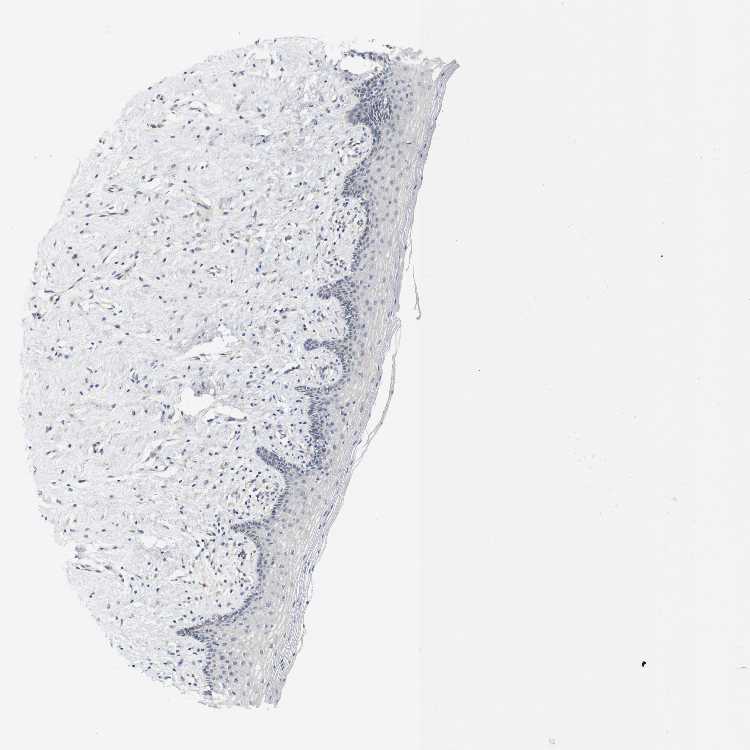

VAGINA - Antibody stainingi

Antibody staining in the annotated cell types in the current human tissue is reported as not detected, low, medium, or high, based on conventional immunohistochemistry profiling in selected tissues. This score is based on the combination of the staining intensity and fraction of stained cells.

Each image is clickable and will lead to virtual microscopy that enables deeper exploration of all samples and also displays staining intensity scores, fraction scores and subcellular localization as well as patient and tissue information for each sample.

Antibody HPA014753

Squamous epithelial cells Low